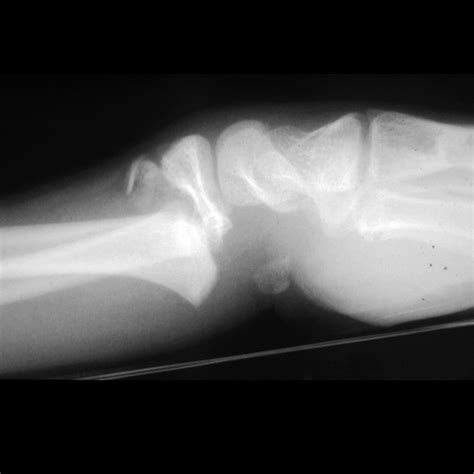

These fractures typically occur in adolescents whose growth plates are still active but nearing closure. The most frequent areas for a Salter Harris Type II injury include the distal radius (the wrist) and the distal tibia (the ankle). The injuries are usually caused by:

• Falls: Landing awkwardly on an outstretched hand or rolling an ankle.

Diagnosing a Salter Harris Type II fracture requires a clinical evaluation followed by medical imaging. Physicians will look for tenderness specifically localized to the growth plate area, accompanied by swelling and a potential deformity if the bone is significantly displaced. The following table highlights key diagnostic comparisons within the Salter-Harris system.